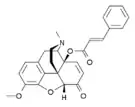

Several semi-synthetic opioids were developed in Germany in the 1910s. The first, oxymorphone, was synthesized from thebaine, an opioid alkaloid in opium poppies, in 1914.[228] Next, Martin Freund and Edmund Speyer developed oxycodone, also from thebaine, at the University of Frankfurt in 1916.[229] In 1920, hydrocodone was prepared by Carl Mannich and Helene Löwenheim, deriving it from codeine. In 1924, hydromorphone was synthesized by adding hydrogen to morphine. Etorphine was synthesized in 1960, from the oripavine in opium poppy straw. Buprenorphine was discovered in 1972.[228]

The first fully synthetic opioid was meperidine (later demerol), found serendipitously by German chemist Otto Eisleb (or Eislib) at IG Farben in 1932.[228] Meperidine was the first opiate to have a structure unrelated to morphine, but with opiate-like properties.[199] Its analgesic effects were discovered by Otto Schaumann in 1939.[228] Gustav Ehrhart and Max Bockmühl, also at IG Farben, built on the work of Eisleb and Schaumann. They developed "Hoechst 10820" (later methadone) around 1937.[230] In 1959 the Belgian physician Paul Janssen developed fentanyl, a synthetic drug with 30 to 50 times the potency of heroin.[211][231] Nearly 150 synthetic opioids are now known.[228]